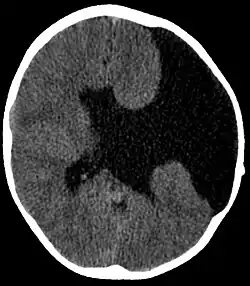

Axial CT scan showing schizencephaly in a 6-year-old child | |

Schizencephaly (from Greek skhizein 'to split' and enkephalos 'brain')[1][2] is a rare birth defect of the brain, characterized by abnormal clefts lined with grey matter that form the ependyma of the cerebral ventricles to the pia mater. These clefts can occur bilaterally or unilaterally. Common clinical features of this malformation include epilepsy, motor deficits, and psychomotor retardation.[3]